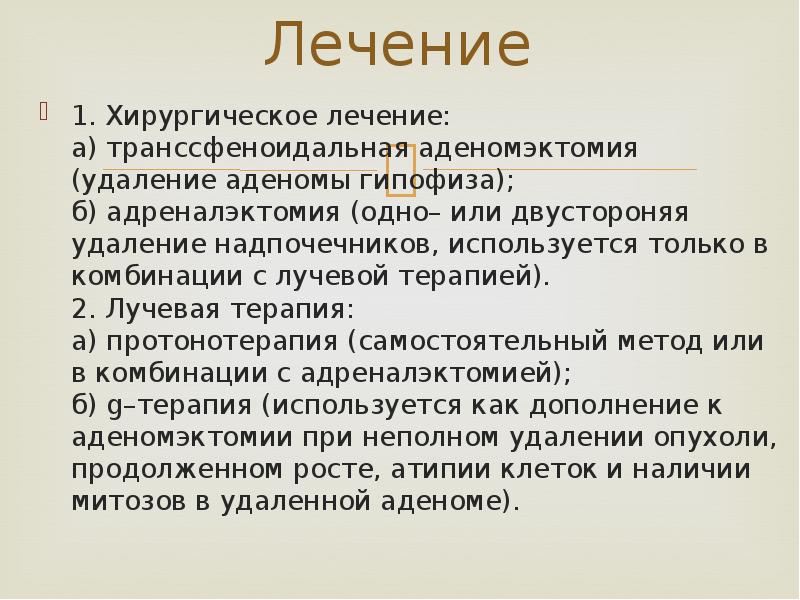

Лечение

1. Хирургическое лечение:

а) транссфеноидальная аденомэктомия (удаление аденомы гипофиза);

б) адреналэктомия (одно– или двустороняя удаление надпочечников, используется только в комбинации с лучевой терапией).

2. Лучевая терапия:

а) протонотерапия (самостоятельный метод или в комбинации с адреналэктомией);

б) g–терапия (используется как дополнение к аденомэктомии при неполном удалении опухоли, продолженном росте, атипии клеток и наличии митозов в удаленной аденоме).